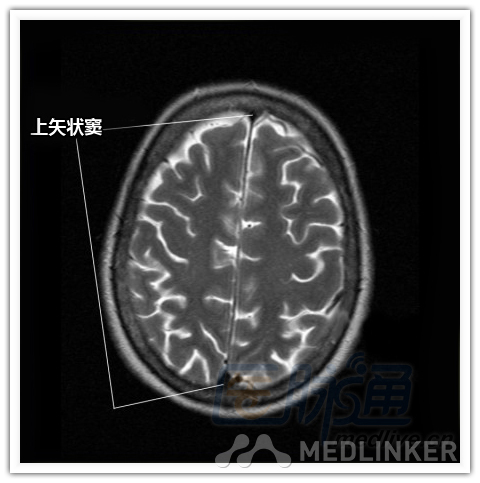

本文将对不同横断位的脑部MRI图像进行标示,主要讲解内容是脑部基本解剖。脑部横断位解剖,尤其是内囊层面的影像学解剖一直是一大重点,一起来学习一下。 现在是内囊层面了,同志们准备好了吗? 本文转载自医脉通。 声明:本文转载是出于提供更多信息以参考使用或学习、交流之目的,不用于商业用途。转载无意侵犯版权,如转载文章涉及您的权益等问题,请作者速来告知,我们将尽快做删除处理。